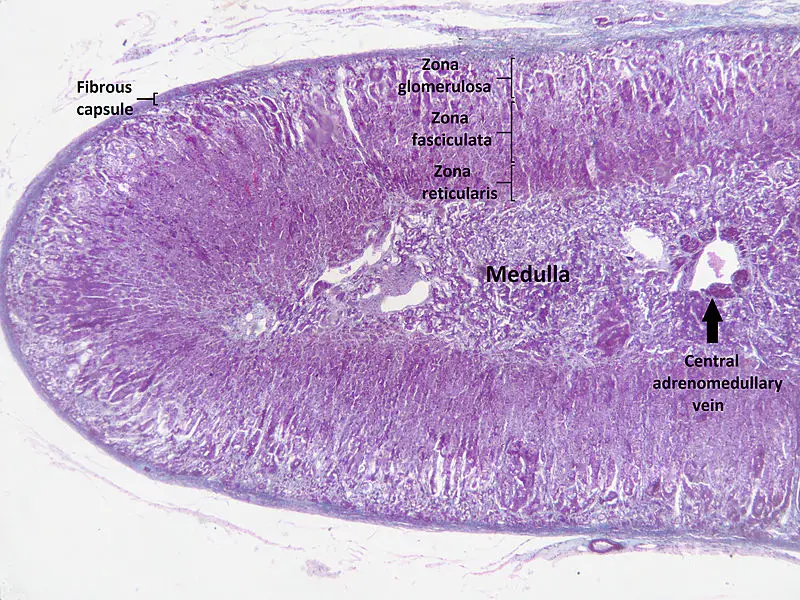

Adrenal Cortex

The largest and outermost portion of an adrenal gland is called the adrenal cortex.

The adrenal gland is composed of three distinct zones which include:

- Zona glomerulosa

- Zona fasciculata

- Zona reticularis

Zona glomerulosa produces mineralocorticoids like aldosterone.

Zona fasciculata creates glucocorticoids like cortisol.

Zona reticularis generates sex hormones like testosterone.